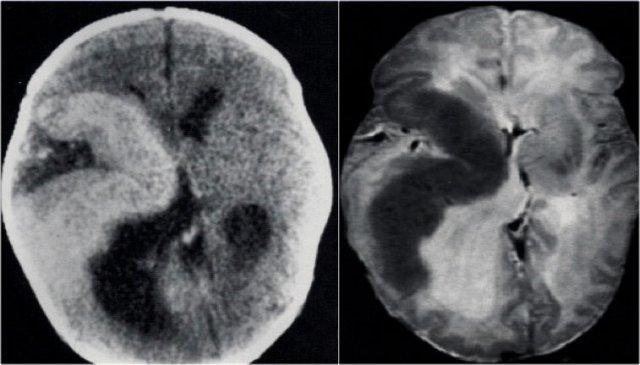

Hình ảnh CT và chuỗi xung T2W trên bệnh nhân hemimegalencephaly bên phải.

Ghi nhận vỏ não dày loạn sản và giãn não thất ở bên bị tổn thương.

Viêm não Rasmussen. Ảnh FLAIR axial và T2WI coronal cho thấy teo bán cầu đại não trái kèm giãn não thất bên.

CT và MRI ở bệnh nhân xơ cứng củ.

Có nhiều nốt vỏ não và dưới màng não thất.

CT cho thấy hầu hết các tổn thương đều bị vôi hóa.